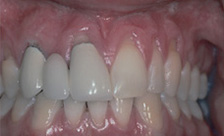

Case #2

| BEFORE | AFTER |